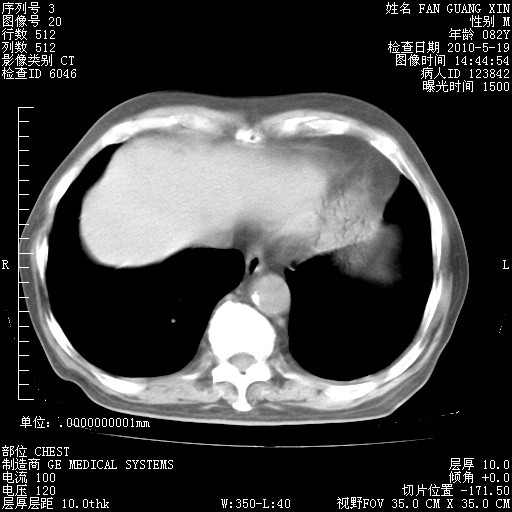

治疗3周后的肺部CT纵隔窗

再治疗10天后的肺部CT

再治疗10天后的肺部CT 纵膈窗

阅读此次胸部CT,肺间质渗出性改变较入院时有吸收。目前从体温、白细胞、中性分叶明显增高,肯定存在细菌感染(发生医院感染哦,若无消化道及泌尿系统等感染的依据,肺部感染可能大)。若你院头孢哌酮舒巴坦钠耐药率较高,同意你的方案,若48小时体温仍高,可考虑使用碳青霉稀类抗菌药物,同时可予超声雾化、注意滴数时加大液体量。白蛋白33.30g/L较低哦,需加强营养等支持治疗。